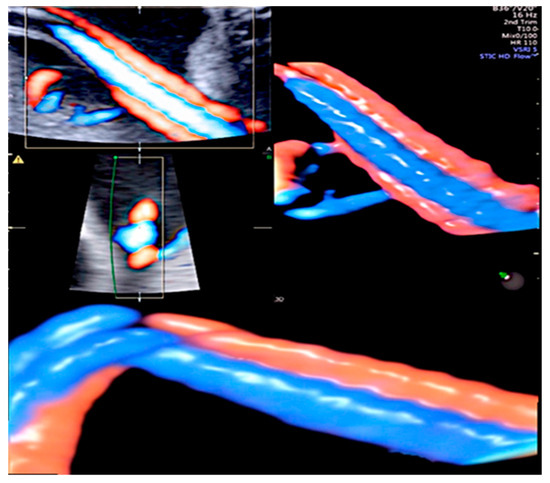

3.2. True Umbilical Cord Knot